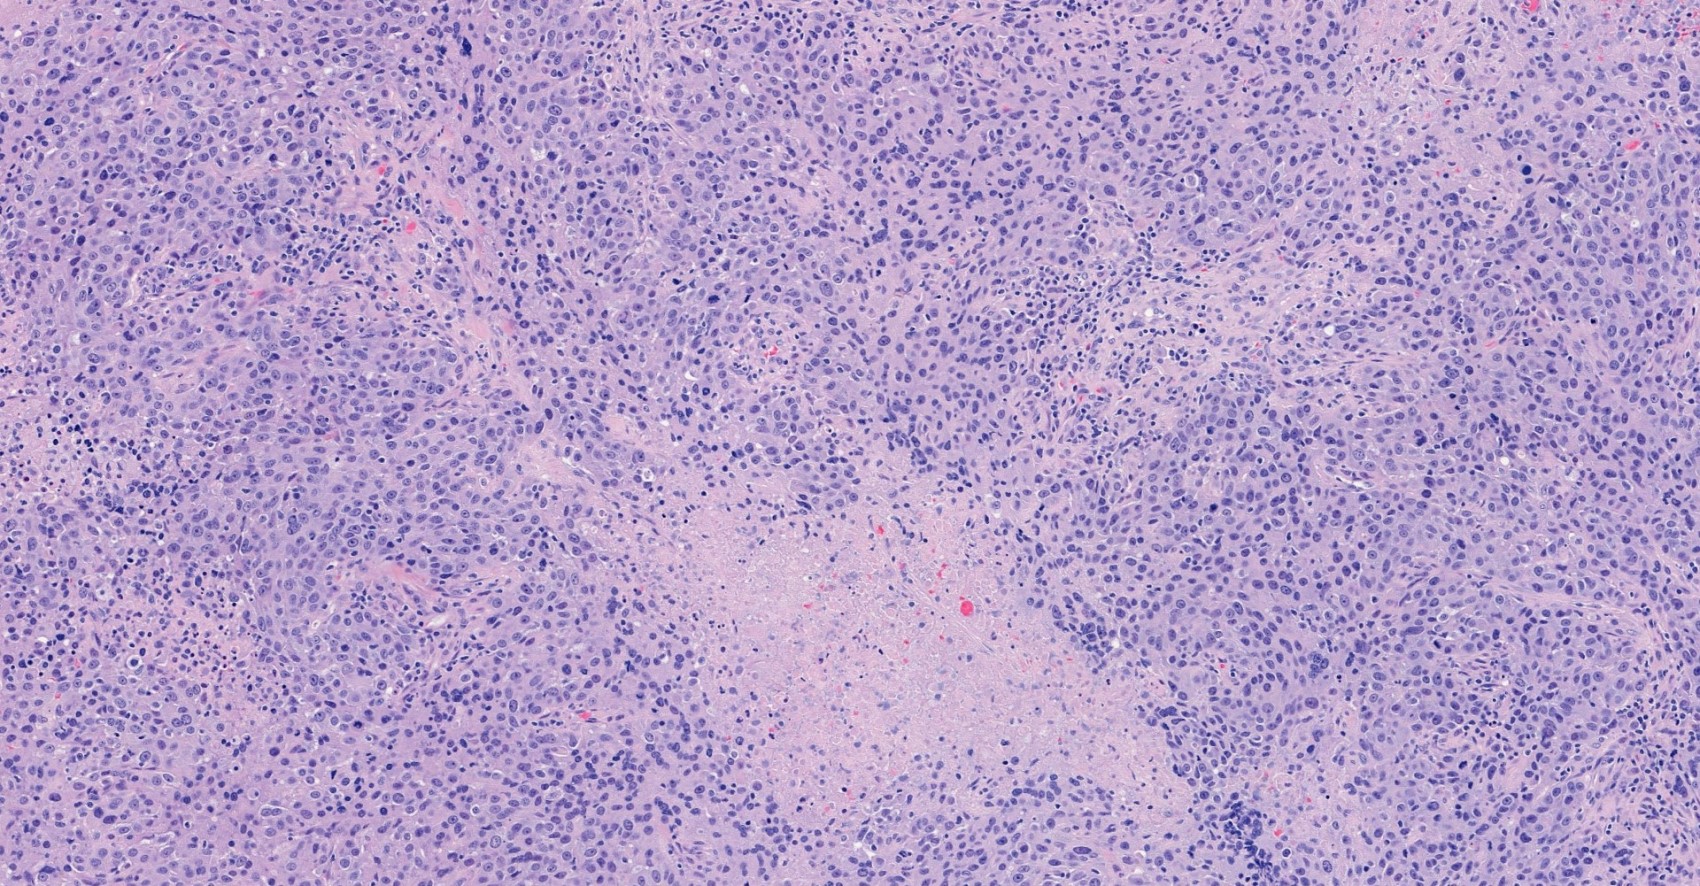

Microscopic (histologic) description

- Histological features of IBC NST vary considerably from case to case and even within the same case

- 2 distinct growth patterns exist:

- Large and solid nests or syncytial infiltrative growth pattern with little associated stroma and an expansive growth that compresses the surrounding stroma (e.g., most basal-like breast cancers)

- Basal-like or medullary-like patterns:

- These include breast carcinomas previous described as medullary-like carcinoma or carcinoma with medullary features, as well as basal-like carcinoma

- These tumors typically show high histological grade, a prominent tumor associated lymphocytic (TIL) infiltrate, a triple negative phenotype and often have basal-like molecular profiles

Microscopic (histologic) images

Contributed by Julie M. Jorns, M.D., Kristen E. Muller, D.O., Gary Tozbikian, M.D. and Emad Rakha, M.D.